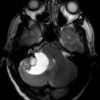

U nguyên bào mạch máu

» Thông tin: Nam giới – 25 tuổi.

» Lâm sàng: Đau đầu + Nôn + Rối loạn thăng bằng.